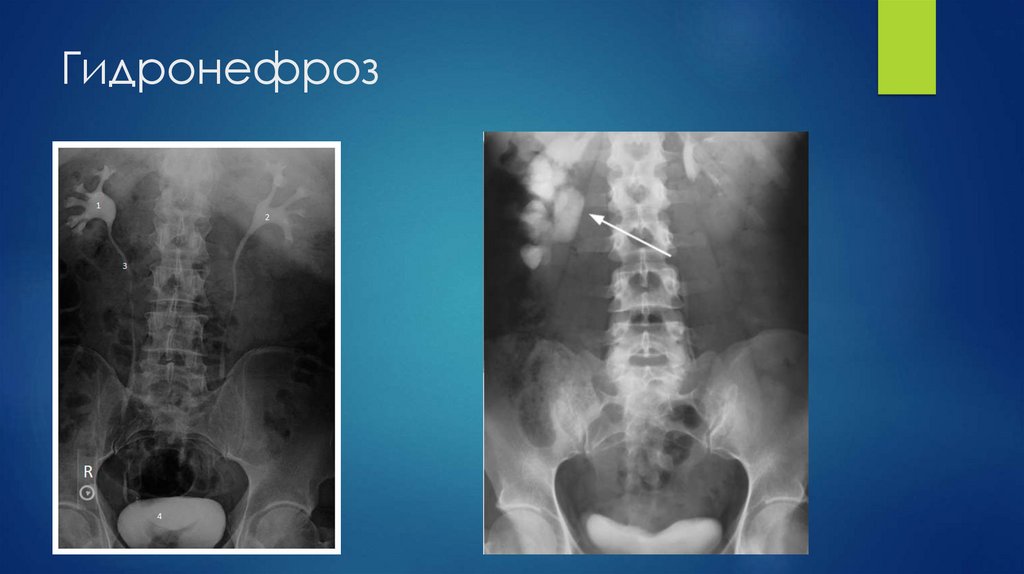

Гидронефроз

47. Гидронефроз

69. Гидронефроз